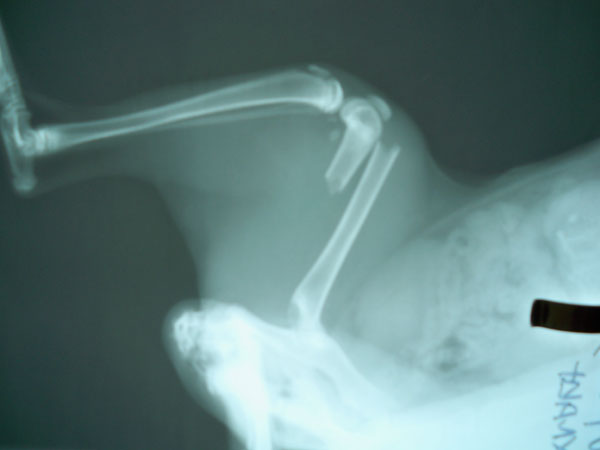

Γάτα DSH με τέλειο κάταγμα στο κάτω τρίτο διάφυσης αριστερού μηριαίου.

Για την αποκατάσταση του κατάγματος μετά την ανάταξη τοποθετήθηκε ενδομυελικός ήλος, ένας ήλος Kirschner εγκάρσια στην

καταγματική γραμμή με φορά απο την πρόσθια επιφάνεια προς την οπίσθια και κατα μήκος τοποθέτηση 4 μεταλλικών ραμμάτων κυκλοτερώς.